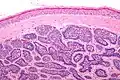

Dermal cylindromas are:

- Dermal lesions consisting of nests of cells that are surrounded by hyaline (i.e., glassy, eosinophilic, acellular) material and have:

- Hyperchromatic nuclei that may palisade (columnar nuclei arranged around the periphery of the cell nests with their short axis tangential to the nest periphery), and

- Cells with lighter staining ovoid nuclei at their centre.

They lack of a significant number of lymphocytes; this differentiates them from spiradenomas.

Micrograph of dermal cylindroma in H&E stain. -